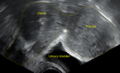

While palpation used in a pelvic examination can typically identify the presence of larger fibroids, gynecologic ultrasonography (ultrasound) has evolved as the standard tool to evaluate the uterus for fibroids. Sonography will depict the fibroids as focal masses with a heterogeneous texture, which usually cause shadowing of the ultrasound beam. The location can be determined and dimensions of the lesion measured. Also magnetic resonance imaging (MRI) can be used to define the depiction of the size and location of the fibroids within the uterus.

A small uterine fibroid seen within the wall of the myometrium on a cross sectional ultrasound view- Two calcified fibroids (in the uterus)